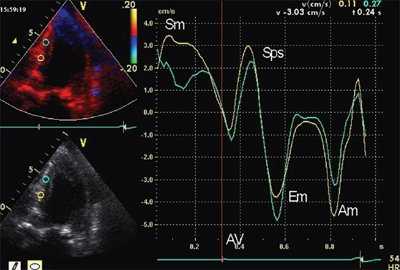

Методика импульсно-волновой ТД

Анализ продольного движения миокарда проводился в верхушечном 4-камерном срезе сердца с синхронной записью мониторного отведения ЭКГ при задержке дыхания пациента в течение 5-10 сердечных циклов (рис. 1). Контрольный объем (5x8 мм) ТД размещался в латеральной и медиальной частях фиброзного кольца митрального клапана (МФК). Точкой начала отсчета временных фаз считали зубец R ЭКГ. Проводился анализ параметров ТД от латеральной (МФКл) и медиальной (МФКм) частей фиброзного кольца митрального клапана: ТМРИ вычислялся по ТД в медиальной и латеральной частях МФК по графикам максимальной скорости движения МФК как отношение разницы временного интервала между началом положительной волны ИВС до начала «Еm» (a’) и временем систолической волны Sm (b’), по формуле:

Рис. 1. Принцип расчета ТМРИ по ТД фиброзного кольца митрального клапана.

ЭхоКГ (стандартная и в режиме тканевой допплерографии) проводилась на ультразвуковой диагностической системе Vivid Five фирмы General Electric (США) секторным датчиком c частотой 3,75 МГц. Исследовалось движение продольных волокон миокарда в проекциях по длинной оси левого желудочка из верхушечного доступа. Тканевая допплерография проводилась в 4-, 3- и 2-камерной проекциях в каждом из 16 сегментов левого желудочка и в 4 точках митрального кольца: у основания заднеперегородочной, боковой, нижней и передней стенок левого желудочка. Оценивались следующие параметры.

- Пиковые миокардиальные скорости: Sm (см/с) - пиковая систолическая скорость; Em (см/с) - пиковая скорость раннего диастолического расслабления; Am (см/с) - пиковая скорость в фазу систолы предсердий.

- Амплитуда постсистолического пика скорости, регистрируемого в фазу изоволюмического расслабления (Sps). Вычислялось отношение скоростей Sps/Sm.

- Форма кривой движения миокарда в течение сердечного цикла. Формы кривых движения миокарда в зависимости от наличия ПСУ подразделялись на 3 типа: "норма", "ступень" и "седло".